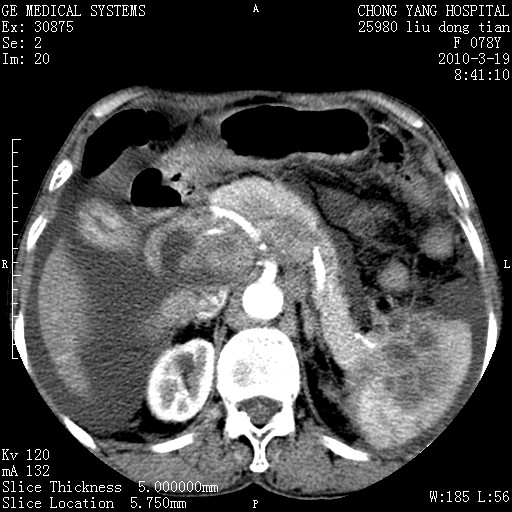

标题: CT25199:F 78Y 腹胀半年 消瘦乏力 [打印本页]

胆囊壁增厚并明显强化,胆囊癌伴多发转移瘤可能性大,淋巴瘤不除外,右肾囊肿,胸腹水.

考虑nhl,肝、脾、腹膜腔及腹膜后多发淋巴结受侵,腹水,右肾囊肿,慢性胆囊炎,右侧少量胸腔积液。

胰头有肿块形成,胰头ca伴肝脾、腹膜腹膜后转移

胆囊有软组织影有强化,支持胆囊癌,肝脾、腹膜后淋巴结转移。

nhl的淋巴结多围绕主动脉,而且主动脉会移位,所以不考虑nhl。

分开来讲:肝左叶、尾叶病灶有不均强化像肝癌;

脾脏病灶无强化,像多发囊肿或淋巴管瘤,不除外淋巴瘤(低强化);

胆囊增生性病变:胆囊癌,腺肌增生症,慢性胆囊炎;

肝门、胰腺头、腹膜后多个团块: 淋巴瘤,转移;

腔静脉肝内段细小有无布加可能?

一元论最好了 淋巴瘤所致改变; 胆囊癌转移不像,胆囊周围肝组织清晰,肝癌淋巴结转移?三元论都不止。

胰头ca伴肝脾、腹膜腹膜后转移!

最后报的胰头癌多发转移,脾脏单独考虑囊肿或淋巴管瘤。